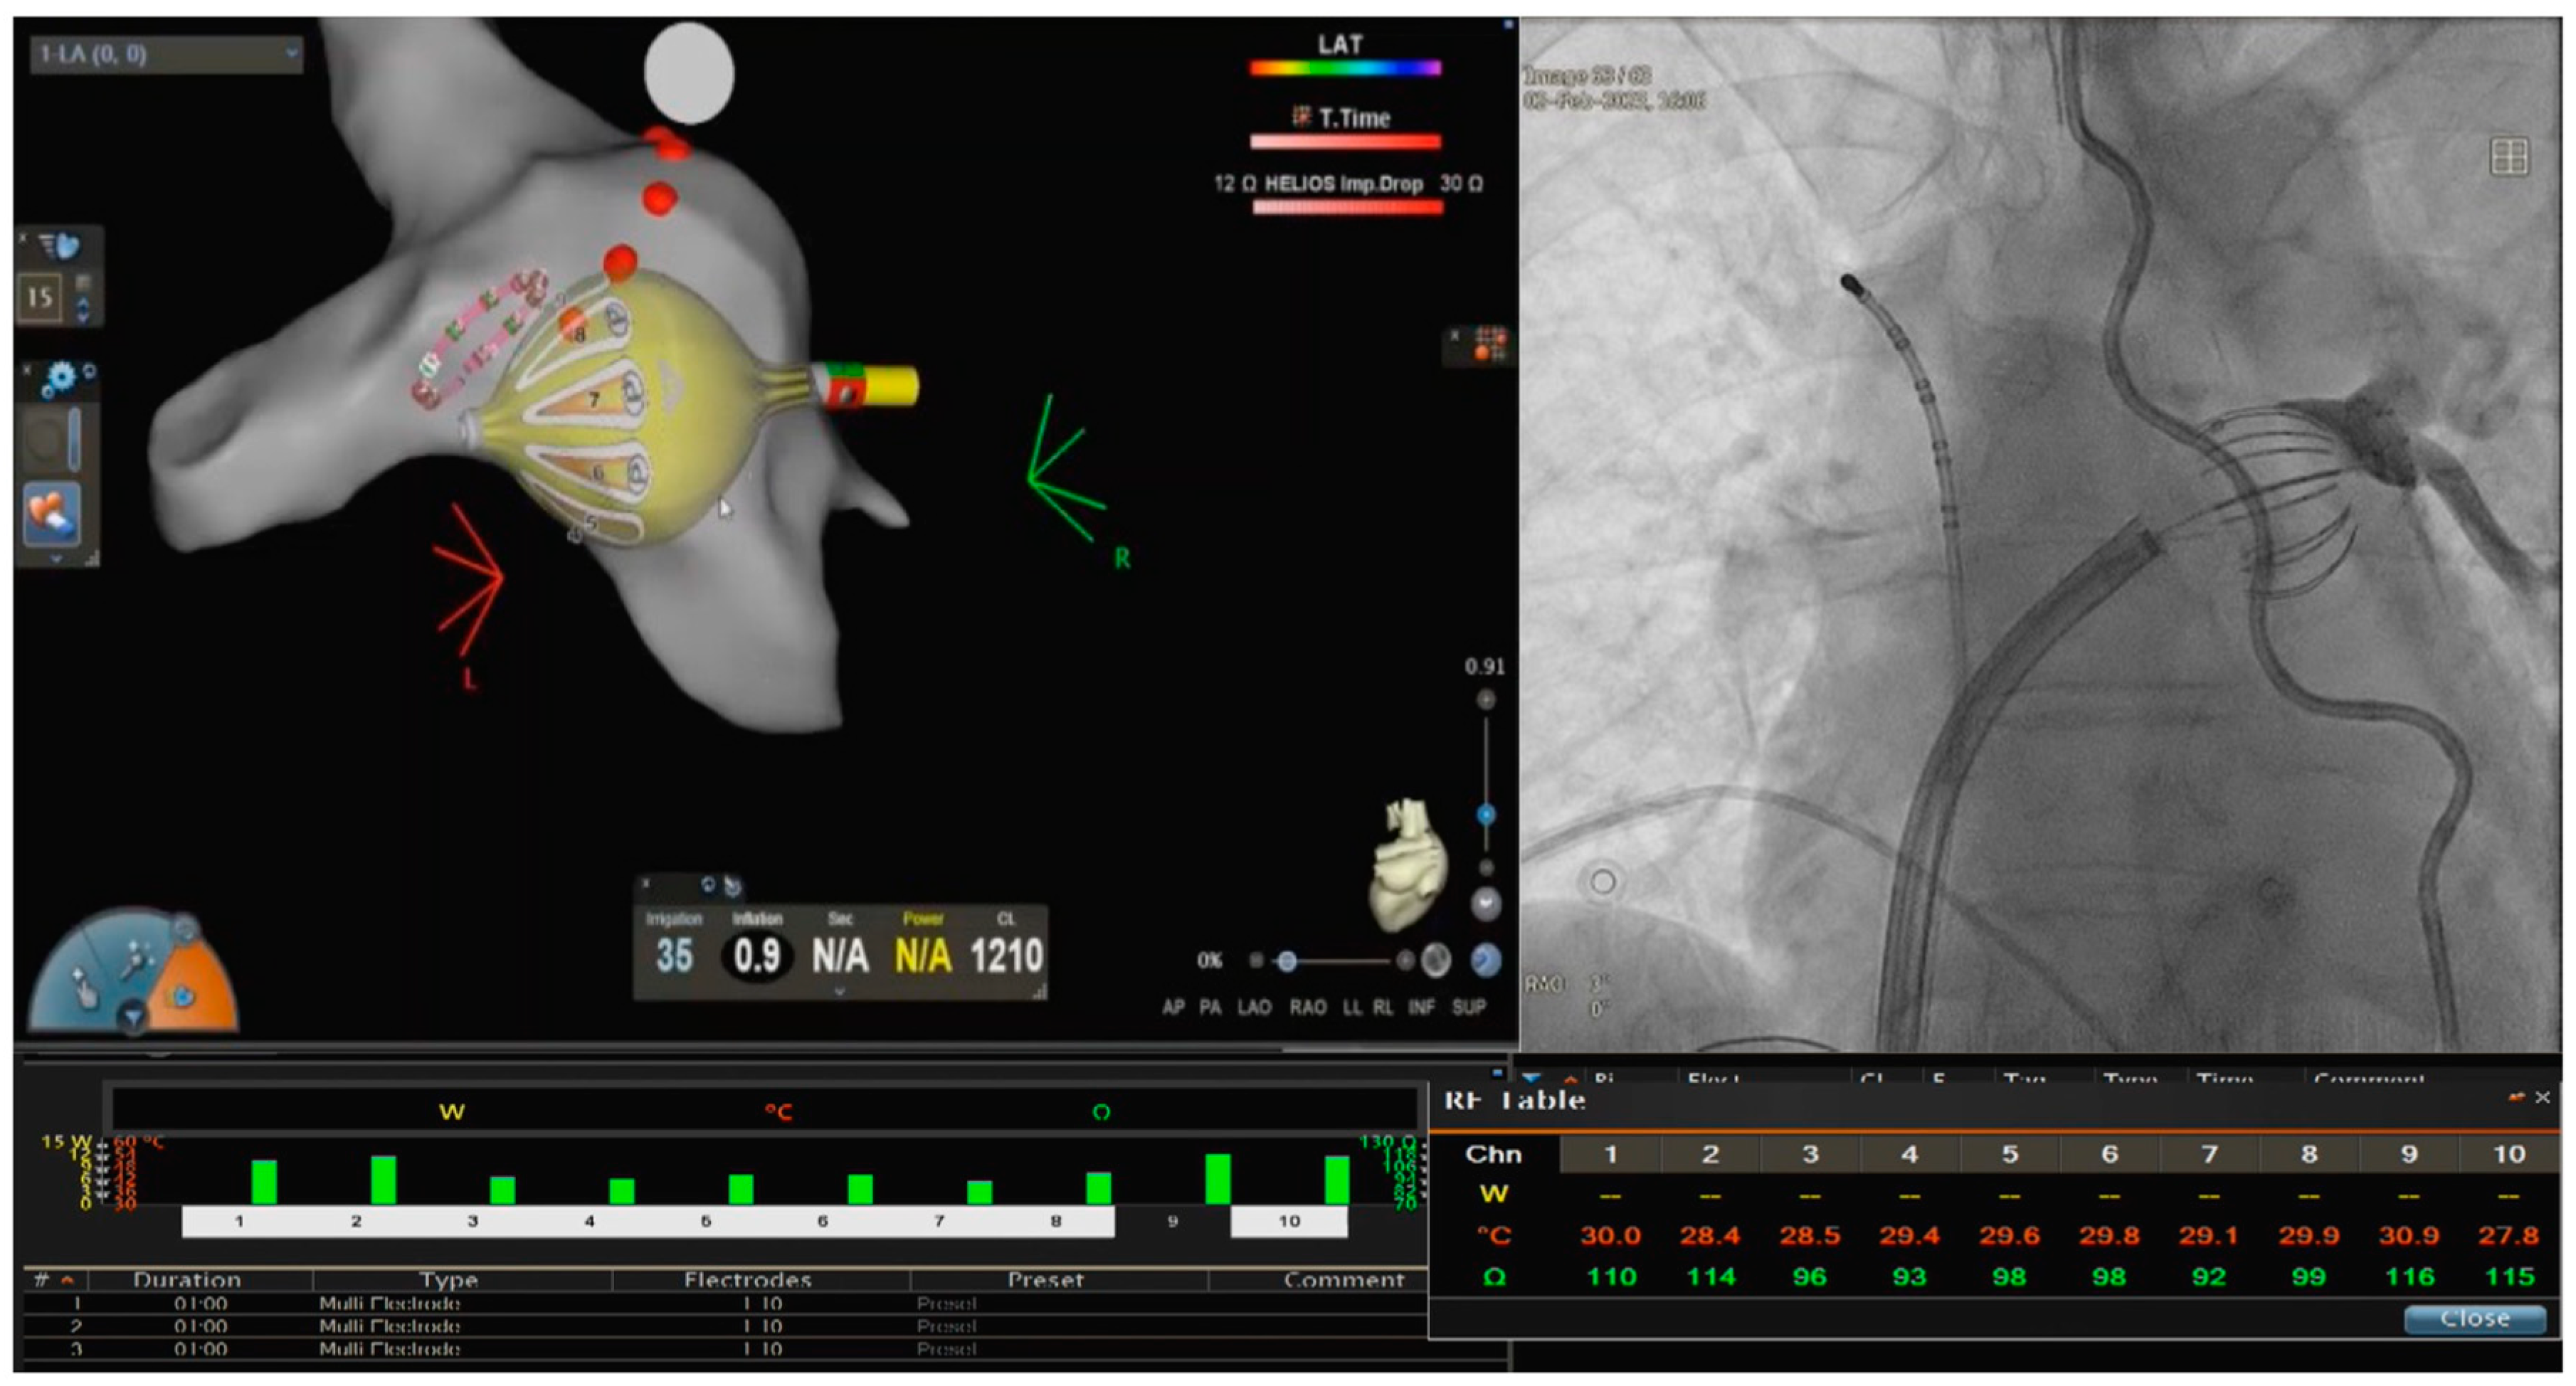

2.2. PVI with the RFB

2.3. RFB Architecture and Lesion Metrics